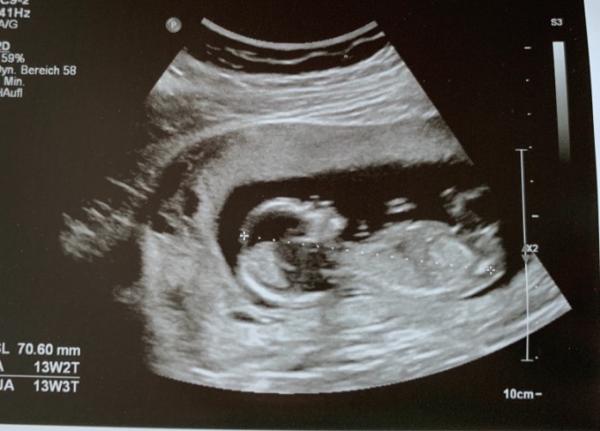

Hallo ihr Lieben, war heute beim Ersttrimester Screening und alles ist super Voraussichtlicher Geburtstermin ist der 10.03.2020 Zum Geschlecht wollte sich die Ärztin noch nicht äußern. Was es wird ist uns auch völlig egal, Hauptsache gesund. Aber neugierig sind wir schon Ich hänge euch mal ein Bild an, erkennt jemand was?

Bild zu Heute Ersttrimester Screening / Erkennt jemand was? - Forum für März - Mamis

Hallo wenn ich mal einen vorsichtigen Tipp abgeben darf würd ich eher sagen sieht aus wie ein Junge hab am 16.9 Termin hoffe auch so sehr das wir das Geschlecht erfahren (uns ist es auch egal was es wird hauptsache gesund aber neugierig ist man dann doch sehr)

Ein schönes Bild aber einen Tipp könnte ich darauf nicht abgeben